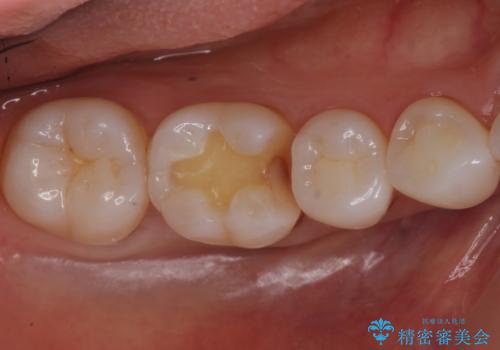

奥歯の虫歯 セラミックインレーでの治療

- 奥歯の黒ずみが気になるとのことで来院されました。

検査の結果、歯と歯の間に小さな虫歯ができていることが確認できました。

白い詰め物をご希望されたため、今回はセラミックインレーでの治療となりました。